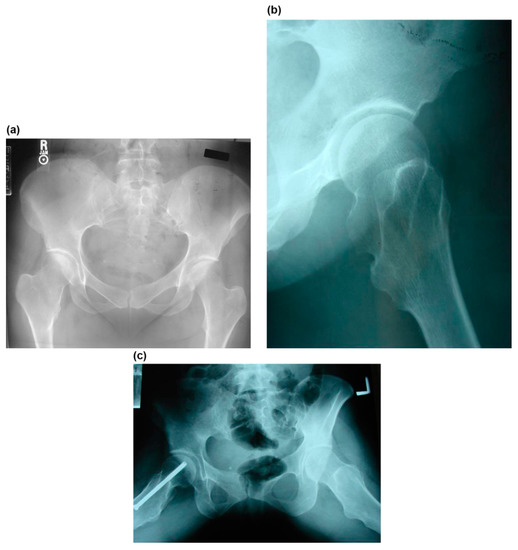

Figure 2.

The images illustrate the case of a 14-year-old boy with Langer–Giedion syndrome (case no. 3). (a) Preoperative anteroposterior radiograph of the left hip shows osteochondromas at the femoral head and a completely dislocated hip. (b) Dislocated hip.